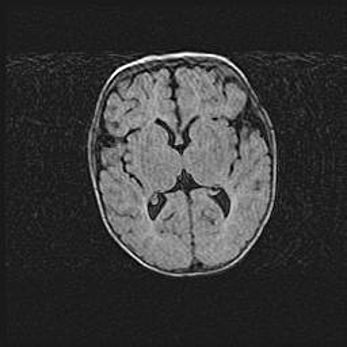

Открытая гидроцефалия.

Возраст: 9 месяцев 12 дней

Вес: 6800 г

Пол: мужской

Окружность головы: 41,5 см

Срок гестации: 28 недель

Гидроцефалия головного мозга у новорожденных имеет характерный признак: опережающий рост окружности головы приводит к визуально хорошо определяемой гидроцефальной форме сильно увеличенного в объёме черепа. Детские неврологи определяют следующие симптомы гидроцефалии у грудничков: выбухающий напряжённый родничок, частое запрокидывание головы, смещение глазных яблок к низу.